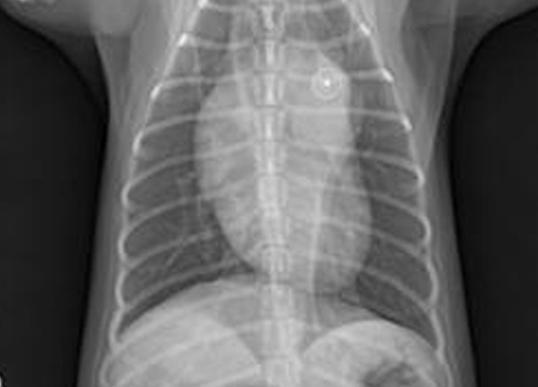

진단을 위해 기본적으로 각종 정밀 혈액검사와 요검사, 방사선검사, 초음파, 내시경 등을 실시하게 되며 치료는 진단된 질병을 바탕으로 약물 치료를 기본으로 하며 관리가 어려운 신장질환의 경우 혈액 투석을 실시하고 있습니다.

증상 치료 이첨판 폐쇄 부전증, 삼첨판 폐쇄 부전증, 폐동맥 고혈압,동맥관 개존증, 부정맥, 폐수종 흉부 방사선 검사, 심전도 검사, 심장초음파 검사, 혈관 조영술,동맥관 개존증 폐쇄술, 심장 박동기 장착

증상 치료 폐렴, 기관/기관지염, 기관협착, 기관지 협착, 고양이 천식 흉부 방사선 검사, 투시 검사, 관련 샘플 및 배양검사, 호흡기 종양 세포 흡인 검사